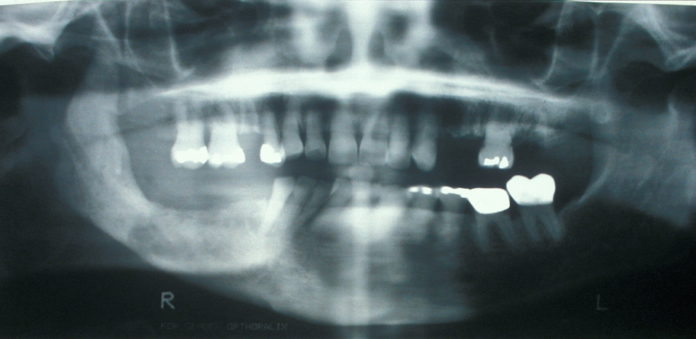

This condition has a number of different names and it occurs in approximately 3 % of routine tooth extractions, and up to 20 % of surgical tooth extractions. Figure 1 shows a dry socket, Figure 2 shows the radiograph of a severe case of dry socket.

Figure 2: Radiograph of a severe case of dry socket, leading to sequestration (formation of a dead piece of bone).